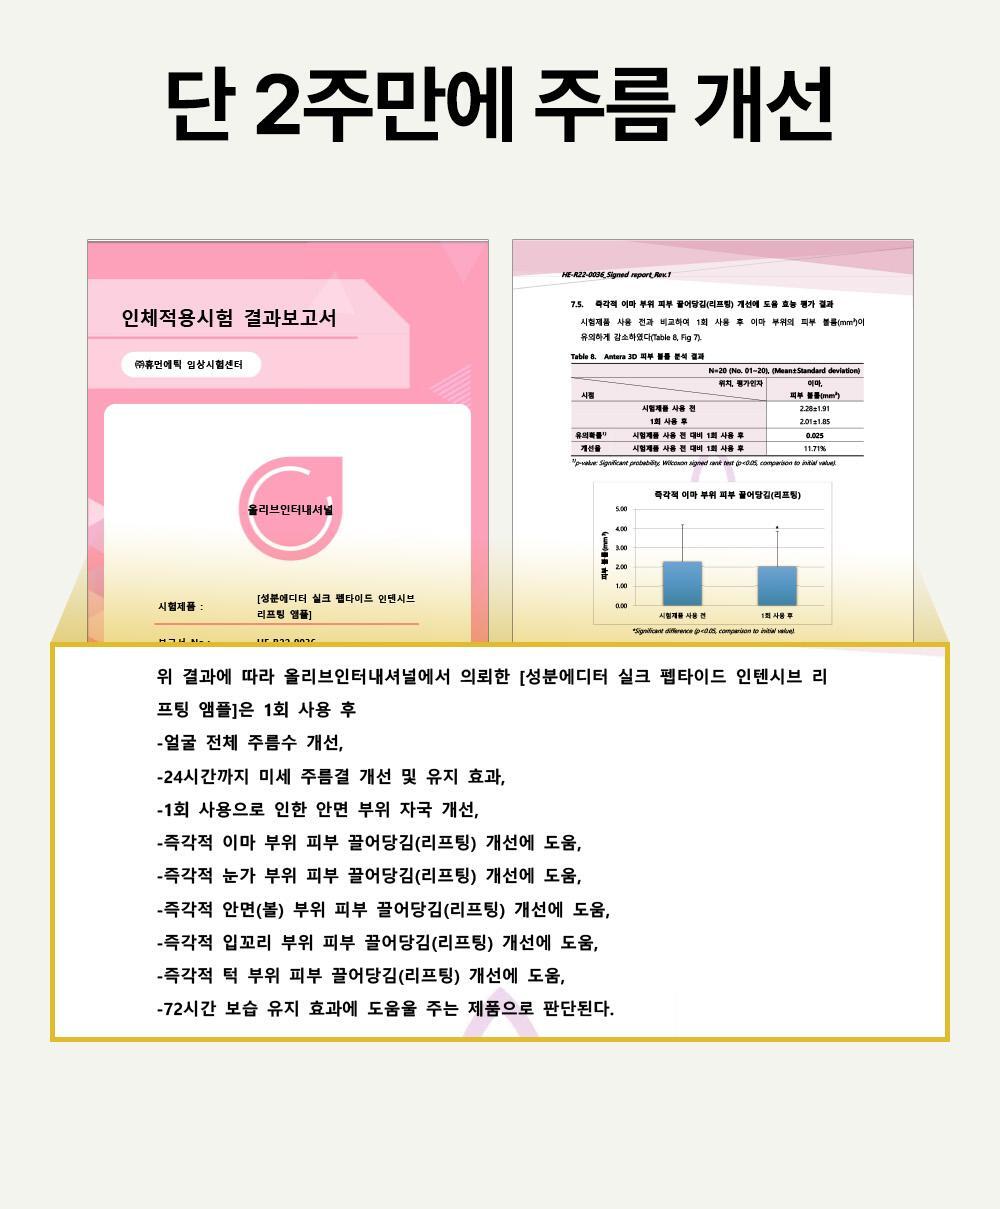

- 已完成人體應用測試。單次使用即可感到提拉緊緻效果。而且這不是暫時的效果。 24小時持續提升力量。持續用更見效果。

成效數據

額部皺紋起始處提升率:83.57%

臉頰深層脂肪突出處提升率:82.11%

嘴角凹陷處提升率:56.73%

下巴皮膚皺摺處提升率:51.64%

眼周易生皺紋處提升率:47.37%

逆齡安瓶 2週密集提升~ 專業級密集護理Sungboon Editor Silk Peptide Intensive Lifting Ampoule 專業級絲蛋白多胜肽高濃縮密集拉提安瓶精華 – 35ml

2週密集使用 彈力驚奇升級

全臉深層滋養 X 肌膚彈力 X 緊緻提升

以「專業級絲蛋白胜肽」與「密集拉提」為核心。

重點為肌膚深層滋養、賦予肌膚彈力,有效帶來全臉、肌膚表層、眼周等多處「拉提」及「緊緻」。

- 即時效果──「2週持續使用」看得見的改變。

- 多重部位護理──「全臉、眼周、臉部肌膚」、「嘴角拉提」、「額頭」、「眉間」、「深層彈力」等問題。